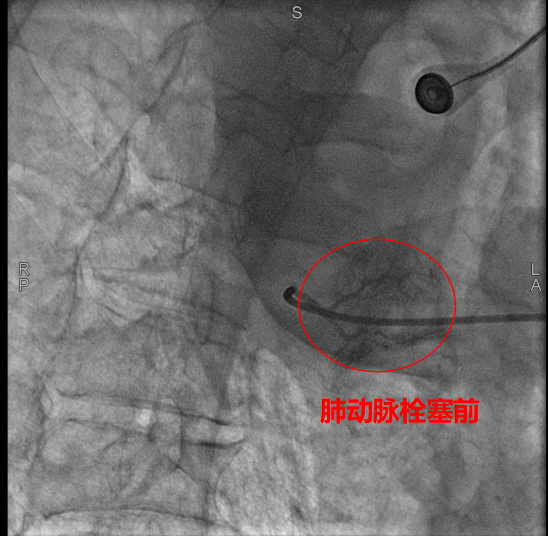

術(shù)中,數(shù)字減影血管造影(DSA)顯示患者右側(cè)支氣管動脈及胸廓內(nèi)動脈增粗紊亂,末梢血管可見造影劑點狀外溢,明確為主要出血責(zé)任血管。團(tuán)隊采用400?μm栓塞微球及560–710?μm明膠海綿顆粒,對出血動脈遠(yuǎn)端實施精準(zhǔn)栓塞,實現(xiàn)“末梢血管封堵”;同時,對肺動脈分支血栓相關(guān)區(qū)域也予以栓塞處理,以全面控制咯血來源。術(shù)后造影確認(rèn)出血完全停止,患者安返病房后未再咯血,胸悶、氣促等癥狀顯著緩解。